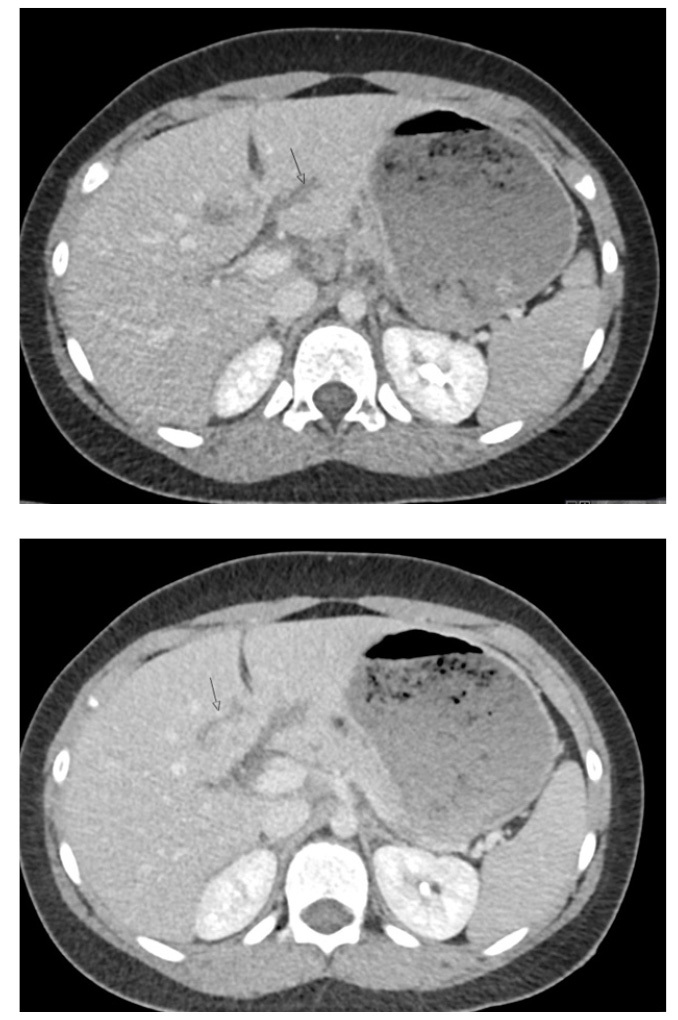

Patients younger than 4 years of age, those in a motor vehicle collision, and those with a positive FAST exam have been shown to be correlated with a higher severity of abdominal injury. The FAST exam in children has a sensitivity of 70%, but this increases when physical exam findings are considered as well.51 Laboratory findings frequently are used to determine the need for imaging as well and are incorporated into some prediction rules, such as the one developed by Streck et al, which was discussed earlier. Abnormal alanine aminotransferase (ALT), aspartate aminotransferase (AST), amylase, and lipase all have been demonstrated to have some utility in predicting solid organ abdominal injury. However, each of these tests has a low sensitivity and specificity. As such, laboratory values should not be used in isolation, but in conjunction with physical exam and FAST findings.52 See Figure 5 for an example of a liver laceration.

Figure 5. Liver Lacerations |

Axial images from computed tomography with intravenous contrast show small lacerations in segments III and IVb of the liver, extending from about 2 cm from either side of the falciform ligament; AAST grade 2. Source: Courtesy of Mark Warren, DO, Dayton Children’s Hospital, Department of Radiology |